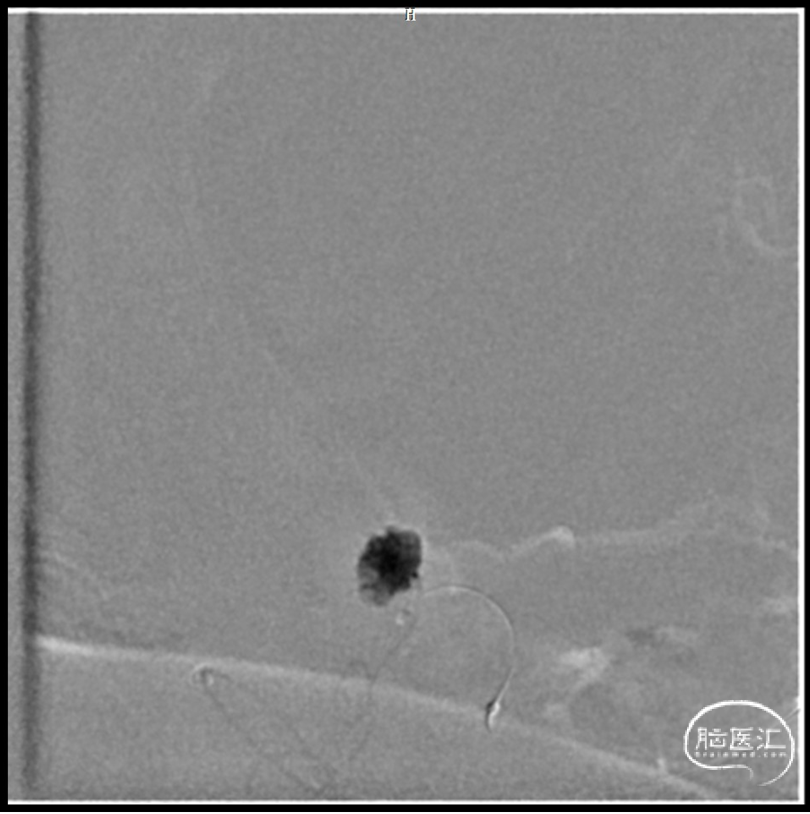

球囊保护下微导管造影证实假性动脉瘤

球囊保护下25%gb栓塞

1.右侧后交通动脉远端假性动脉瘤;

后交通动脉在向后稍内行走的过程中发出两组约2 -8条(以4条为多见)细小的中央支(图1)。前组供应丘脑下部、丘脑腹侧部;视束前部和内囊后肢。后组主要供应丘脑底核。这些中央支之间虽然存在吻合,但其中一支阻塞后,因有效的侧支循环难以建立,故多产生相应供应区的梗死。该病例栓塞假性动脉瘤所在中央支没有症状,考虑为假性动脉瘤导致该中央支缺血耐受和血管代偿。